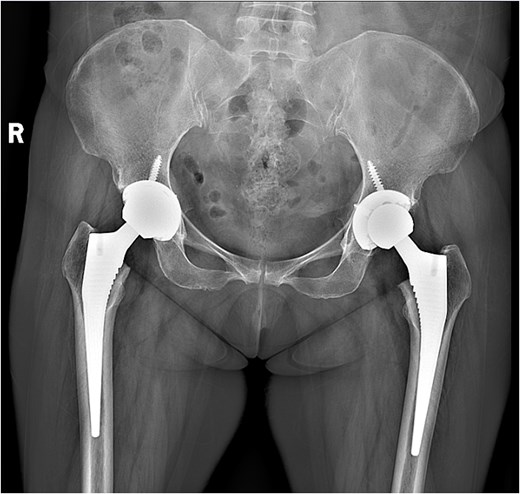

A 47-year-old woman, weighing 65 kg with a height of 158 cm and a body mass index (BMI) of 26 kg/m2, came to our hospital with chief complaints of bilateral hip pain and difficulty walking for 1 year and underwent left THA and 1 week of right THA because of bilateral avascular necrosis and collapse. X-ray of the pelvis of both hips revealed bilateral avascular necrosis and collapse (Fig. 1). A posterolateral approach was used for the bilateral hips in the lateral decubitus position. The implant consists of a Pinnacle cup (DePuy), DELTA ceramic liner and ceramic femoral head (BIOLOX DELTA), and collarless Corail stem (DePuy). After fixation of the acetabular cup, the senior surgeon placed the ceramic liner into the metal shell by hand. Unfortunately, the liner was not placed in the centre position and became stuck. The edge of the tilted ceramic is slightly greater than the cup, perhaps only 5 mm or less. The surgeon attempted to remove the liner by tamping the edge with the plastic impactor using light force several times, but the process of doing so fractured the ceramic liner (Fig. 2). The alumina ceramic fragment of the liner was removed carefully (Fig. 3), and the site was irrigated well. A 32-mm polyethylene liner and a ceramic femoral head were implanted. Full weight-bearing was allowed on postoperative day 1 with a walking aid. The patient remained hospitalized for 8 days to monitor closely for early perioperative complications. Sutures were removed on the seventh day, and the laboratory results indicated an absence of infection. At the 2-month postoperative interval, the patient achieved a successful outcome, with complete resolution of her preoperative symptoms as well as a return to all her activities of daily living (Fig. 4).